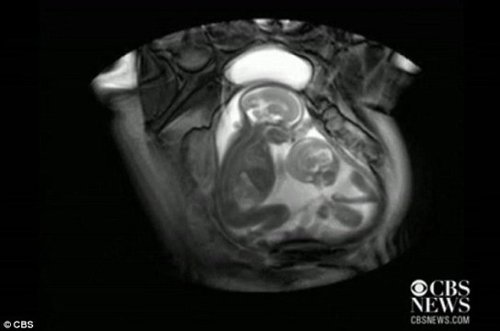

核磁共振成像技术显示,一对双胞胎在妈妈肚子里拳脚相向“掐架”

中新网12月1日电 据外媒报道,近日一段对孕期20周孕妇的核磁共振的扫描视频显示,一对双胞胎还在妈妈肚子里就开始挥动手脚 “掐架”,令人感到神奇又搞笑。工业加湿机

据报道,英国伦敦帝国理工学院(Imperial College)胎儿保健中心本打算用核磁共振成像仪来诊断共享一个胎盘和同一个血液供应系统的胎儿双胞胎输血症候群(twin transfusion syndrome)情况,却意外拍到了子宫中双胞胎的“大战”。机房专用加湿机

视频显示,画面右边个子稍小的胎儿在对左边稍大的胎儿挥动手脚,“拳打脚踢”,似乎打算用身体争得更多空间。而后者比较安分,也动了动嘴,缩了一下身子。